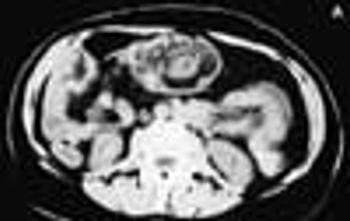

For 2 months, a 73-year-old man had experienced dysuria, pneumaturia, and foul-smelling urine. He had an attack of diverticulitis a year earlier. At that time, he underwent a barium enema study, which showed multiple sigmoid colonic diverticula with spasm.